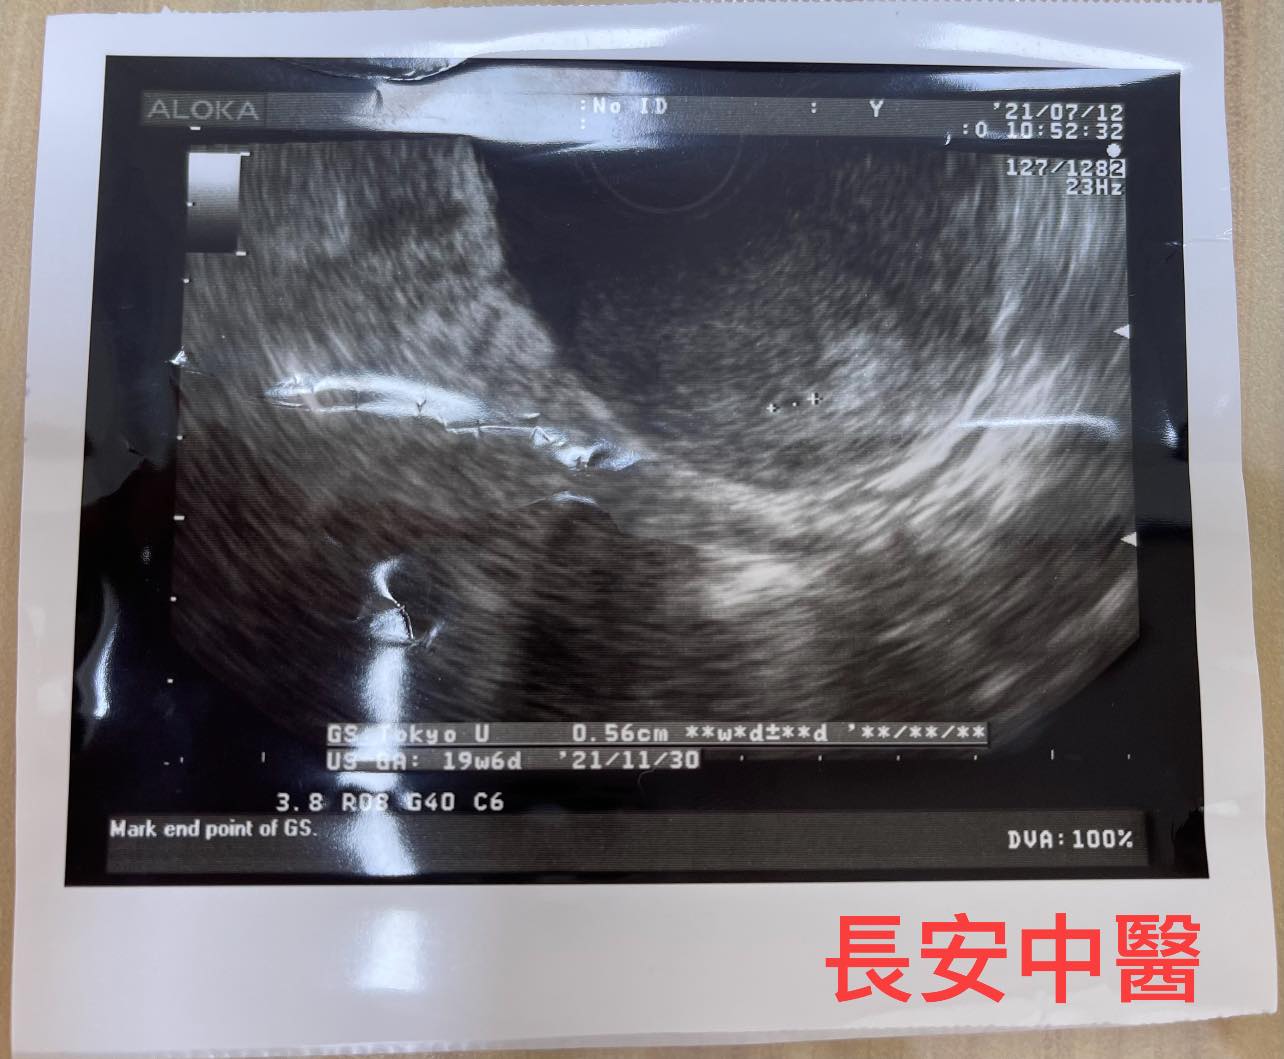

G小姐自然流產後,經常有疲倦感、食慾不振,恢復月經週期後,月經來潮時,經痛嚴重,經過蘇醫師詳細的診察,辨證為氣血兩虛夾瘀型,經過中藥治療後,G小姐精神體力、食慾增加,經痛減輕。服用中藥同時搭配測量基礎體溫,使高溫期穩定長達14天,再進行計畫性受孕,這次排卵後,順利懷孕,目前胎兒已大於12周。

圖片為患者懷孕時分享給蘇醫師的超音波檢查照片。